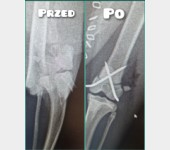

Jest szansa na uratowanie Bajki, ma złamaną prawą tylną łapką i pogruchotaną w kilku miejscach miednicę. Niestety - nasze możliwości finansowe się wyczerpały, życie dość mocno sie ze mną obeszło w ostatnich latach i nie mam generalnie nic. Dziś wydaliśmy wszystkie skromne oszczędności, żeby opłacić leczenie Bajki do tej pory.

Kochani, dzięki Waszym wielkim sercom Bajka dziś pomyślnie przeszła operację - DZIĘKUJEMY ????♥️???? Wielkie brawa dla lekarzy z lecznicy Cztery Łapy w Jeleniej Górze ! Koszt operacji wyniósł 3260 PLN plus każdorazowa wizyta kontrolna 30 PLN plus koszty dodatkowe za miesiąc, tj. wyjęcie śrub, leki, rehabilitacja. Dziś zapłaciłem 3000 PLN, załączam rachunek. Następne załączę przy kolejnych opłatach. Bajka wysyła miaubuźki (. ❛ ᴗ ❛.)